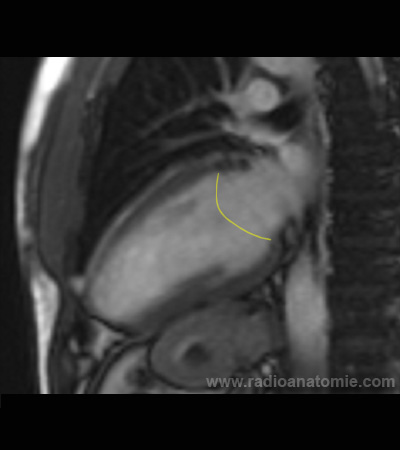

Radioanatomie et plans de coupe en IRM cardiaque

Valve mitrale

Oreillette gauche

Ventricule gauche